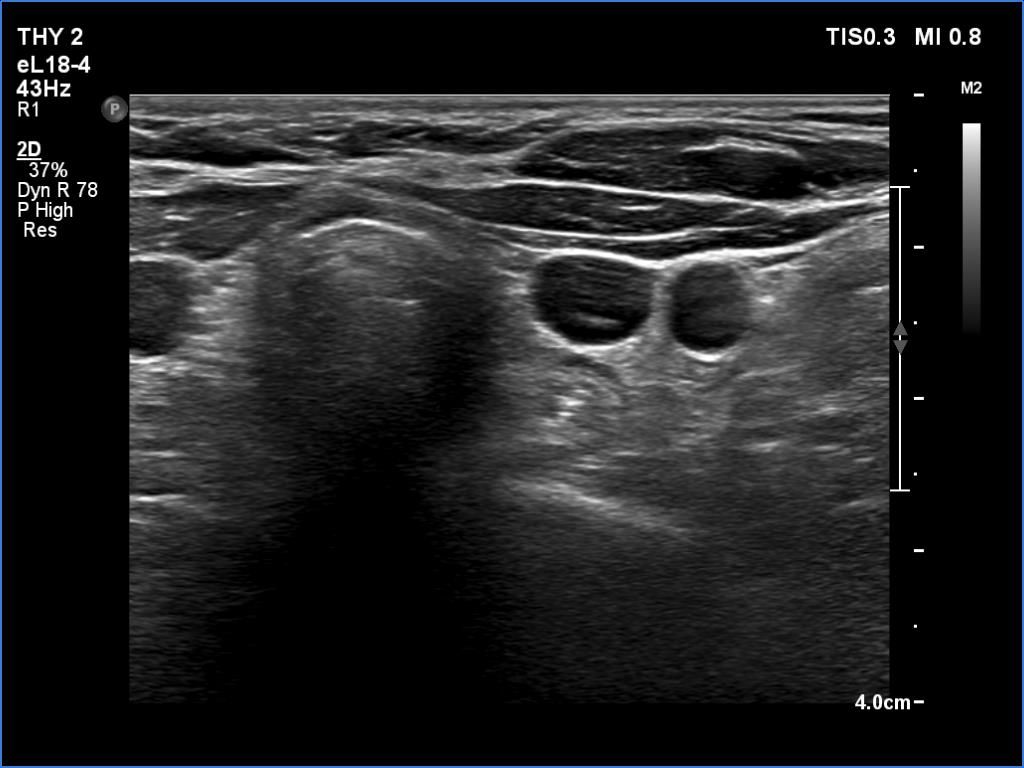

Ultrasonography revealed a cystic lesion in the left thyroid bed. The dimensions of the cyst were 8x6x13 mm, width, depth and length, respectively.Suggestion: to continue with the daily 125 microgram levothyroxine. TSH in a year, in the event of pregnancy at once.

Ultrasonography was unchanged. Connective tissue was found in the upper part of the left thyroid bed while there was a cystic lesion in the lower half. On the location, the lesion corresponded to a parathyroid cyst. The dimensions of the cyst were 8x6x13 mm, width, depth and length, respectively.Suggestion: to increase the dose of the levothyroxine to daily 150 micrograms. TSH in 6 weeks.